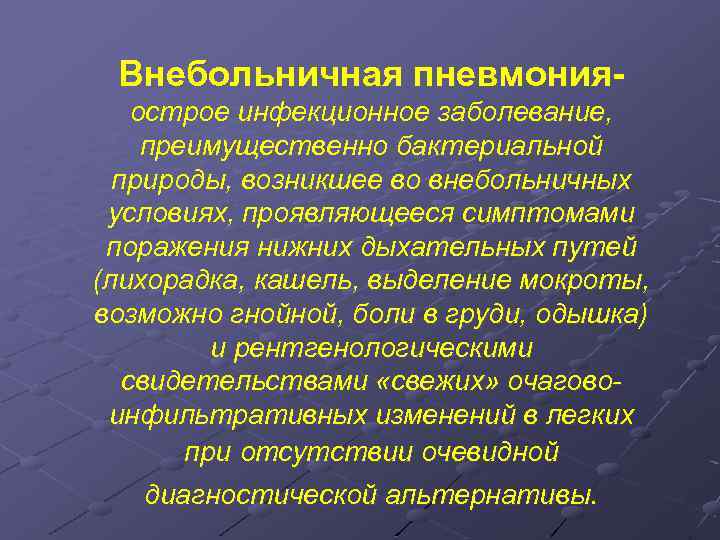

Острая внебольничная пневмония по МКБ-10: признаки и примеры